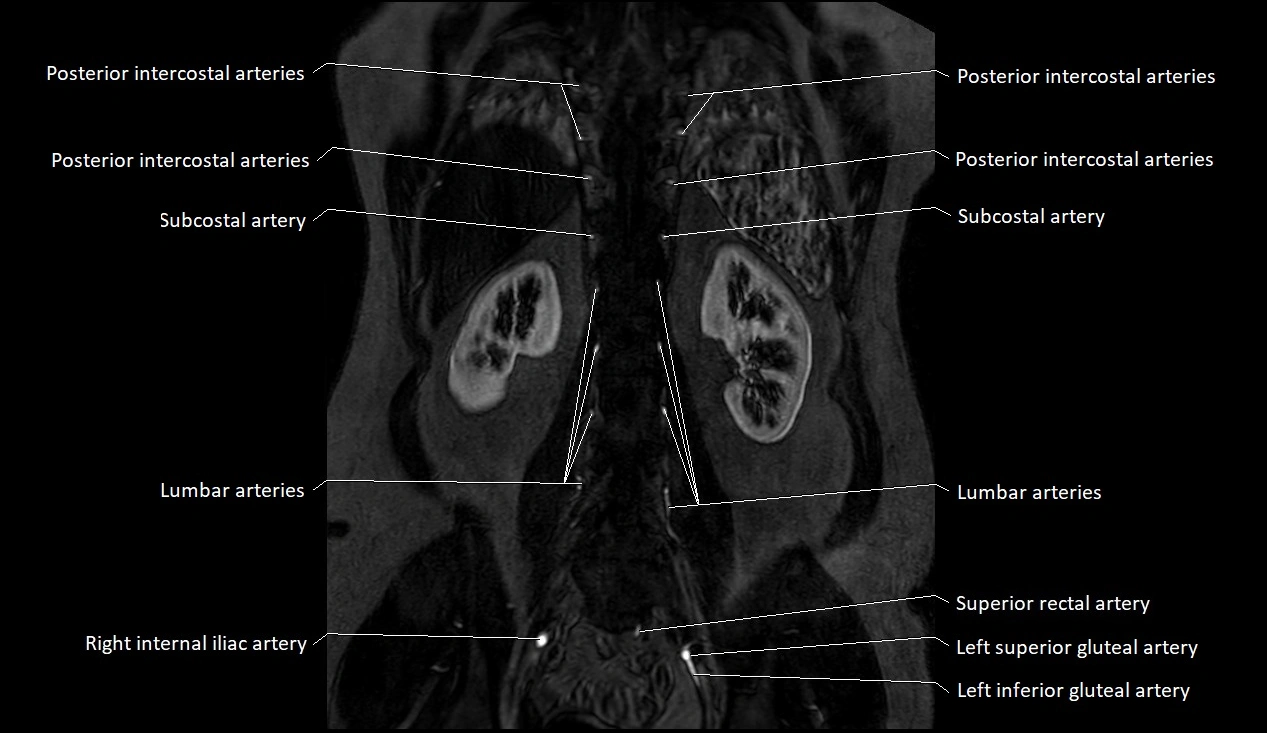

CT images

image